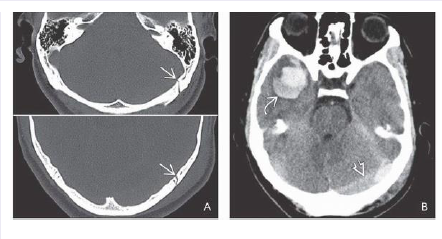

What structure has been fractured?

What other findings are seen on the 2nd box?

(Top) Bone CT in a 26-year-old man who fell 25 feet onto his head shows a diastatic fracture of

the left lambdoid suture. (Bottom) The fracture continues superiorly, following the lambdoid suture above

the insertion of the tentorium. 2-22B. NECT scan shows a mixed-density posterior fossa EDH . Note

“contre-coup” contusion of the right temporal lobe with mixed attenuation hematoma suggesting rapid

bleedin

What are seen?

More cephalad scan in the same patient shows that the EDH extends above the tentorium behind

the left occipital lobe. 2-22D. CTA was obtained because CT findings suggested venous EDH with laceration

of the left transverse sinus. (Left) Coronal, (right) sagittal reformatted images nicely show that the EDH

extends below and above the tentorium, displacing cortical veins as well as elevating and compressing the

left transverse sinus.